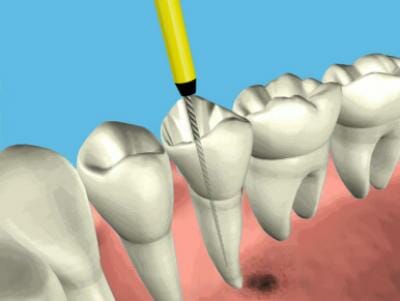

Bent u bij de jaarlijkse tandartscontrole geweest en moet er een wortelkanaalbehandeling worden uitgevoerd? Dan